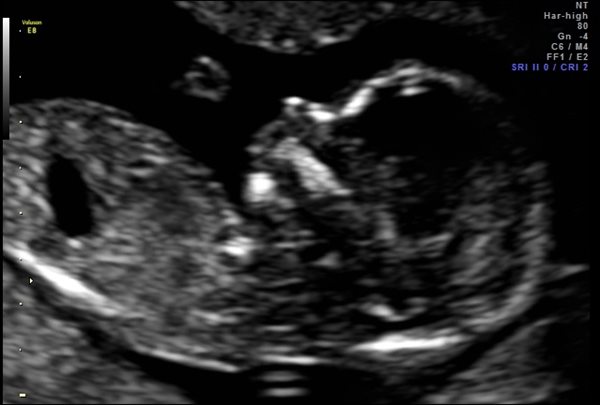

Figure 1 demonstrates a ‘green flag’ feedback plot with most measurements being within the ideal range. Sonographers should ideally aim to achieve a green flag rating, which equates to less than 0.1mm bias in measurements.

Figure 1: A feedback plot with a green flag for normal bias and spread. Courtesy of NHS FASP (2022).